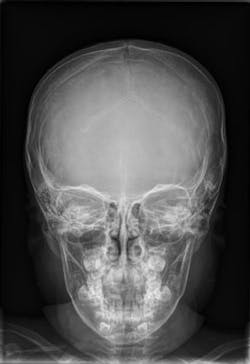

Radiographic evaluation of peripherally-inserted central catheter (PICC) line placement has always been a challenging aspect of critically-ill patient care, so MUSICA2’s advanced image processing capabilities make the process much easier for the clinician and the patient, said Greg Cefalo, US Digital Imaging Unit Business Manager, Agfa HealthCare.

"Dense areas in the radiograph and/or complex anatomical structures can easily mask the PICC line, making it difficult and time consuming to verify the exact placement,” he said in the press release. “We've created a special version of MUSICA2 image processing that instantly enhances the catheter detail, causing the line to pop in the image and be clearly identified; this eliminates time-consuming re-processing and more importantly, can reduce the need for additional patient exposures."

Propriety image processing algorithms in the software are tuned to enhance the visibility of the catheter in a way that improves edge and tip detection. It shows soft tissue and boney detail in a single image across the entire dynamic range, without having to make manual adjustments. The software then creates a second image with the enhanced detail so there is little or no need for manual reprocessing, which not only saves time, but also lowers the patient dose and exposure.